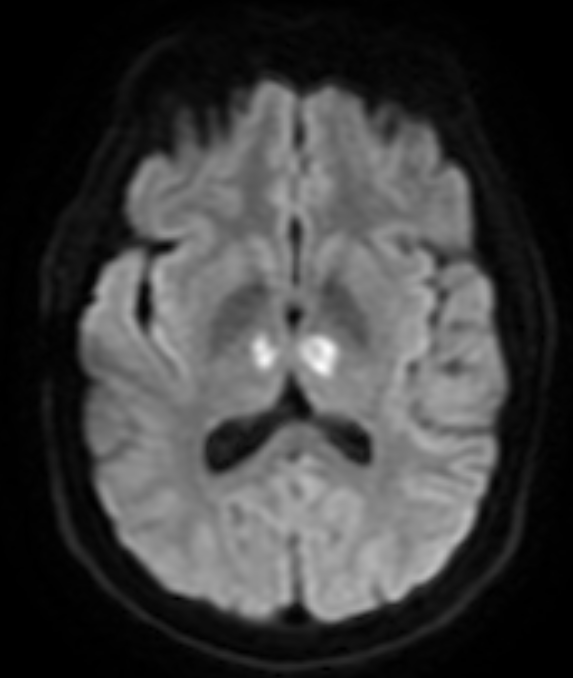

In neurology, the Artery of Percheron is a rare anatomical variant in which the blood supply for both medial thalamic nuclei arises from a single small arteriole at the top of the basilar artery, rather than from two individual arteries. An embolism or occlusion in the Artery of Percheron causes simultaneous bilateral infarcts. The medial thalami are necessary for maintenance of consciousness and attention, therefore artery of percheron stroke can cause an abrupt decrease in level of consciousness, confusion and drowsiness.